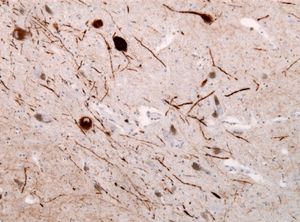

루이 신경돌기는 질병에 걸린 뉴런에서 발견되는 비정상적인 신경돌기이다.[20] 이는 루이소체에서 발견되는 것과 유사하게 비정상적인 알파-시누클레인 필라멘트와 과립성 물질로 구성되어 있다.[20][31]

루이소체가 있는 DLB(루이소체 치매) 사례의 루이 신경돌기. 염색 적용: 면역조직화학

루이 신경돌기는 루이소체처럼 시누클레인병증(Synucleinopathy)의 특징적인 병리 소견 중 하나로,[21] 루이소체 치매, 파킨슨병, 다발계 위축증(MSA)과 같은 질환에서 나타난다.[21][31] 또한, 알츠하이머병 환자의 해마 CA2-3 영역에서도 발견될 수 있다.[21][31]